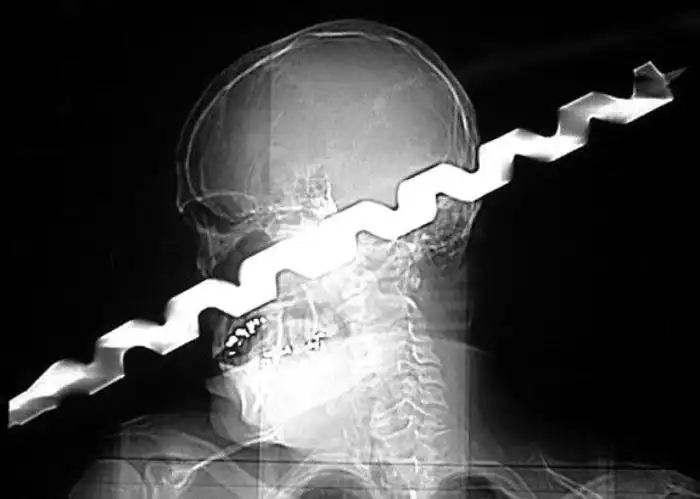

Необычные предметы в теле людей на рентгеновских снимках

На рентгеновских снимках людей порой можно обнаружить самые необычные предметы, которые находятся в их теле.